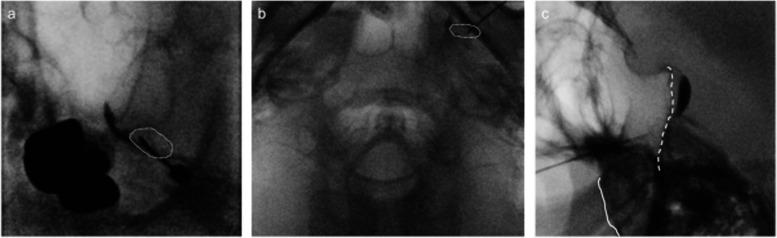

A 49-year-old male with multiple sclerosis exhibited persistent dull pain and paroxysmal electric shock-like pain in his bilateral maxillary molars and mandible. He was diagnosed with trigeminal neuralgia due to multiple sclerosis. Due to severe side effects, it was difficult to achieve adequate pain control with medication alone. By performing low-temperature radiofrequency thermocoagulation and pulsed radiofrequency of the Gasserian ganglion while monitoring masseter muscle contraction, a satisfactory and rapid analgesic effect was obtained without masticatory atonia.

一名49岁的多发性硬化男性患者双侧上颌磨牙和下颌出现持续性钝痛和阵发性电击样疼痛。他被诊断为继发于多发性硬化的三叉神经痛。由于严重的副作用,仅靠药物难以实现充分的疼痛控制。通过在监测咬肌收缩的同时对半月神经节进行低温射频热凝和脉冲射频治疗,获得了满意且快速的镇痛效果,且未出现咀嚼肌麻痹。